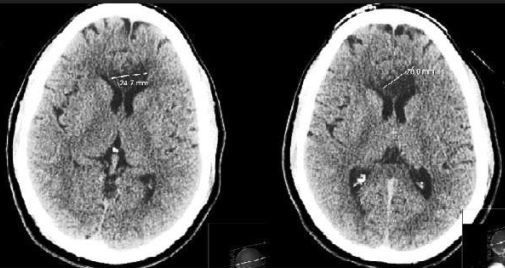

On the second day of rehabilitation, the patient became aphasic and lethargic; he was also found to have abulia (loss or deficiency of willful initiative or drive) and left-sided apraxia (loss of the ability to carry out learned purposeful movements). A second CT brain scan showed a bilateral corpus callosum lesion (Figure). Administration of tPA was deferred because of the recent stroke. Initial differential diagnoses of glioblastoma multiforme, lymphoma, and multiple sclerosis were entertained on the basis of the CT findings. The results of diffusion-weighted MRI of the brain were consistent with corpus callosum ischemic stroke crossing the midline.